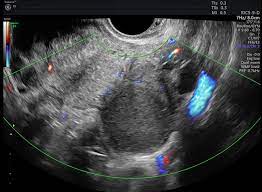

Sometimes cysts on an ultrasound can be mistaken for endometriosis, says dr. It is unclear what causes ovarian cancer, but risk factors include a family history of the condition and mutations in certain genes. There is evidence to suggest that endometriosis may slightly increase a woman's risk of developing this form of cancer. Ovarian cancer is a tumor that forms on one or both of the glands that store eggs in the female reproductive system. I am 42 years old, and have been experiencing perimenopausal symptoms for about 4 years.

The fact that endometriosis can mimic the symptoms of a urinary track infection (also known as a bladder infection) can sometimes trip doctors up a bit. The main difference is, while it can be a serious condition, endometriosis is not deadly or fatal. Many women are told that they. Ovarian cancer can indeed be mistaken for endometriosis. The symptoms for ovarian cancer and endometriosis are much the same so i am worried and confused. However, this does not explain other cancer risk among women with endometriosis. They share some things in common, such as causing cells. Although ovarian cancer occurs at higher rates in women with endometriosis, the overall lifetime risk is low to begin with. Ovarian cancer is a tumor that forms on one or both of the glands that store eggs in the female reproductive system. But even with those cancer types, the risk is still lower than 1%. But if endometriosis patients have abdominal bloating or fullness, changes in bladder or bowel habits or abnormal uterine bleeding, they should consult with their gynecologists. shih adds that abdominal sonography and a ca125 blood test, which measures the cancer antigen in one's blood, can also determine a patient's risk for ovarian cancer. Like with bladder infections, endometriosis can cause painful urination, so these symptoms can. However, endometriomas can sometimes pose an even greater diagnostic challenge, as they can be mistaken for functional ovarian cysts which grow each month as part of a woman's normal monthly ovulatory cycle.